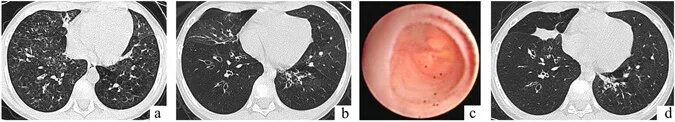

Бронхиолит причины